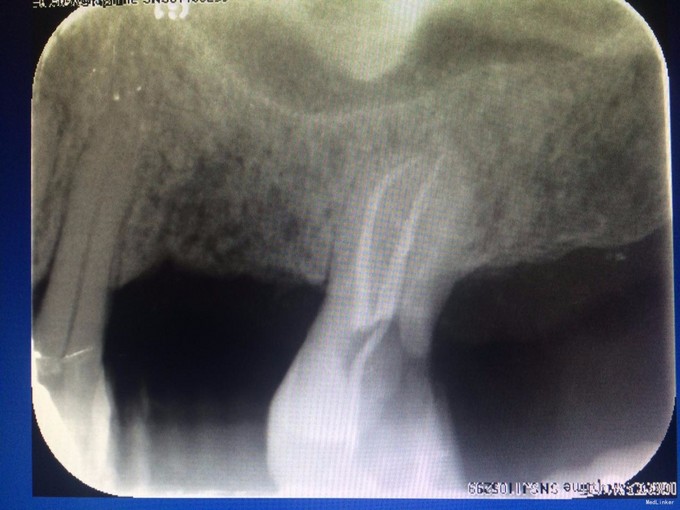

检查:#27 he 面见大量黑色腐质,叩(—),松(I),探(+),冷热测迟缓性疼痛,去除刺激后依旧持续一段时间,电测有活力,牙龈稍红肿,#26,#28已拔除,拔牙创愈合可。 X线示: #27根尖未见明显阴影,牙槽骨吸收至根中1/3

诊断:#27慢性牙髓炎 治疗: #27碧兰麻下开髓、揭全顶,寻找根管口,拔髓,次氯酸钠和双氧水交替超声冲洗,测量工作长度,根管预备,封Ca(OH)糊剂2两周,ZOE暂封。两周后复诊检查,患牙无叩痛,患者无不适,暂封存。去暂封,次氯酸钠和双氧水交替超声冲洗,再次测量工作长度,干燥,热牙胶充填。树脂充填治疗。